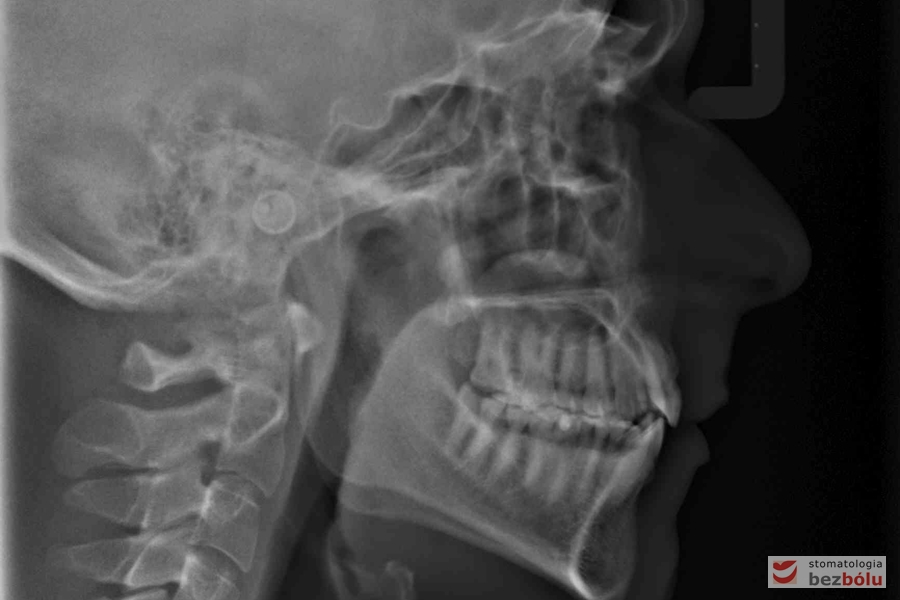

Diagnostyka cefalometryczna - ocena położenia szczęk i zębów względem siebie

Diagnostyka cefalometryczna – ocena położenia szczęk i zębów względem siebie